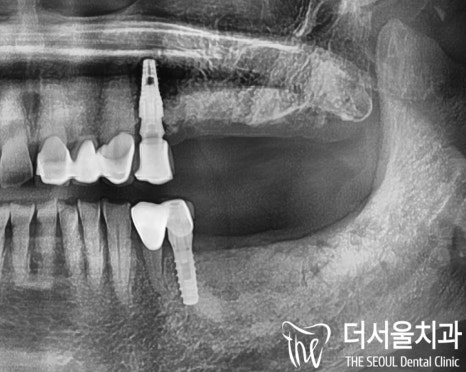

왼 : 발치 후, 오 : 임플란트 식립 후

다시 돌아와서 현재 건강을

고려하여 위와 같이 발치하였고

위아래 무사히 임플란트 식립을 마쳤습니다.

위 사진은 오른쪽 치료를 위한

엑스레이인데요,

오른쪽 위아래 어금니 역시 잇몸뼈가 많이 낮아지고,

뿌리 끝 염증은 물론 치아의 동요도 있어

마찬가지로 발치를 진행했습니다.

이후 구강 환경 고려 후

인공치근인 픽스처를 심고

임시치아까지 올려 드렸습니다.